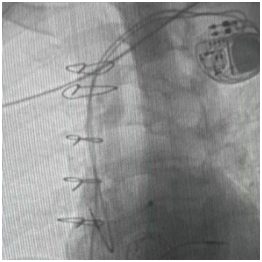

经过心脏外科、心内科、麻醉科、超声科等多学科反复论证,团队最终决定:采用经导管介入技术,一次性完成三大操作——球囊扩张狭窄的三尖瓣、植入新的生物瓣、同时安置永久起搏器。

永久起搏器植入术

手术台上,心脏大血管外科陈文生团队通过细致的影像引导,将球囊送至原有瓣膜处进行扩张,随后将新的生物瓣精准释放在预定位置。最后,在心脏稳定的状态下,顺利植入了永久起搏器。整个过程中,患者生命体征平稳。

术后超声显示,李爷爷三尖瓣的返流量从“大量”降至“少量”,心脏血流得到根本改善。起搏器工作正常,心跳恢复稳定节奏。术后恢复顺利,水肿等症状明显消退,恢复情况良好。目前,李爷爷已康复出院。